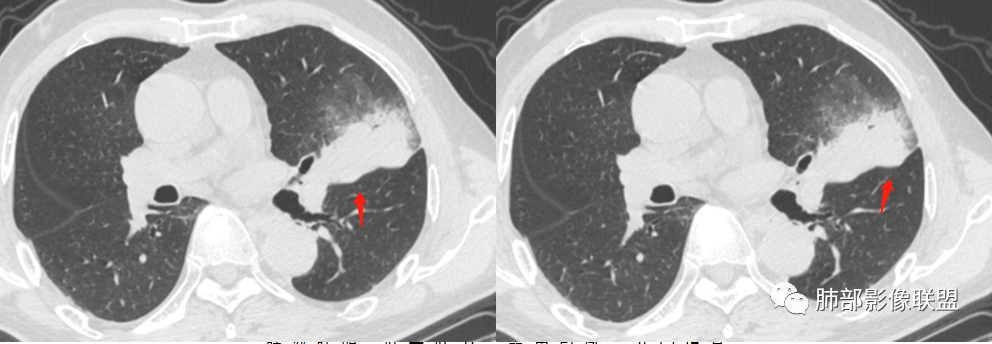

这三个月后的

发了后面这个,就不用纠结了,直接秒了。

大雄:

我只是要告诉大家,不是二元,就是肿瘤,没有什么感染,磨玻璃都没消失。

周围磨玻璃影是飘出去的粘液,也是肿瘤的一部分吧?

@小赵 这个不一定是粘液,很可能还是周围癌性浸润。看术前复查,原磨玻璃区呈明显小叶间隔增厚改变了。说明还是癌性淋巴浸润。

@温附一影像科,傅钢泽 应该是STA(气腔播散)加癌性淋巴管炎。

5、周围磨玻璃,3个月后逐渐转为密实,应符合当初附壁生长为主,且逐渐向实体成分转换。

6、病变长轴平行且受限于胸膜,外围大内带小,符合外朝内发展病变。“腔内结节状明显强化”加之支气管改变有力支持新生物诊断。如此大范围边界不清的磨玻璃影让人浮想联翩。如此大范围病灶,肺门纵隔未见肿大淋巴结也让人意外。